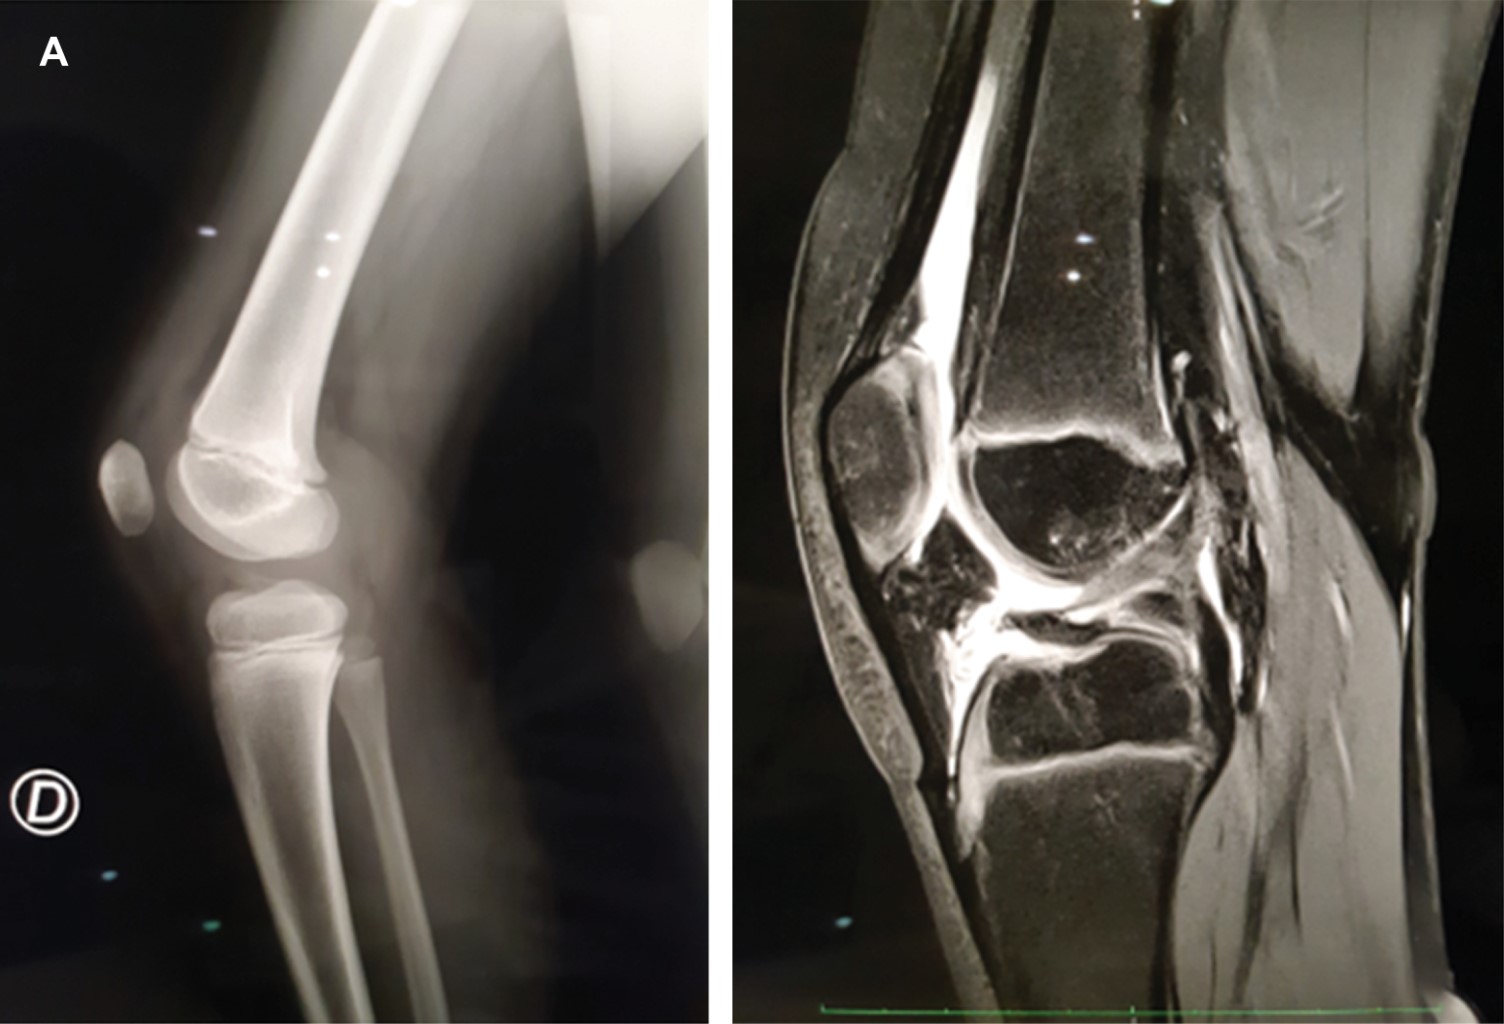

Paciente masculino de 11 años que acude a valoración tras presentar caída mientras jugaba en un brincolín, con lo que desarrolla dolor y aumento de volumen de rodilla derecha así como equimosis leve y limitación para el apoyo con la extremidad. Se realizan estudios de imagen (Figuras 1 y 2), entre ellos radiografía de ambas rodillas en la que se describe irregularidad de la meseta tibial de rodilla derecha, compatible con avulsión de la espina tibial. La tomografía computarizada mostró fractura de meseta tibial en topografía de inserción de ligamento cruzado anterior. La resonancia magnética reporta fractura por avulsión de la apófisis espinosa anterior de la tibia, y zonas de contusión ósea con lesión osteocondral grado 1-2 de cóndilo femoral lateral y plataforma tibial, además de meniscopatía intrasustancia medial grado 2.

La clasificación de estas lesiones está basada en el grado de desplazamiento en la radiografía lateral. Meyers y McKeever las clasifican en tres tipos. Las fracturas tipo 1 no están desplazadas; las fracturas tipo 2 están desplazadas, pero conservan una bisagra posterior intacta; las fracturas tipo 3 están completamente desplazadas. Un cuarto tipo de fractura se usa para describir un patrón con conminución de la espina tibial.1 De acuerdo con tal clasificación, al paciente correspondió una fractura de espina tibial tipo 3. La complementación diagnóstica con resonancia magnética adquiere importancia ante la sospecha de fracturas de espina tibial tipo 1. Se ha encontrado una baja sensibilidad para detectar rupturas parciales de ligamento cruzado anterior con este estudio.5 Además, la resonancia magnética puede facilitar la planeación preoperatoria al definir de manera más adecuada la topografía de la avulsión así como lesiones adicionales de tejidos blandos que requieran manejo. Pueden existir lesiones asociadas en 40% de los casos. Hasta 35% de los casos reportan atrapamiento meniscal en el sitio de fractura, y contusiones óseas en 90%.1